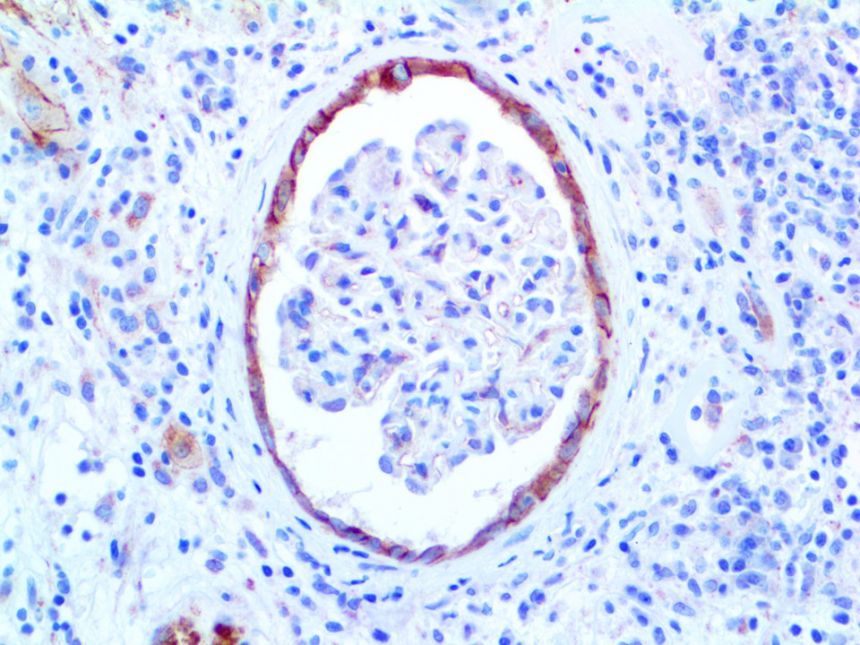

This activation induces inflammatory monocytes to highly express IL-6, starting a localized and then systemic cascade effect that results in hyperproduction of IL-6, which accelerates the inflammatory process. Because IL-6 also increases vascular permeability, excessive levels cause blood vessels to become very leaky. This, along with clotting factors released from vascular endothelial cells, stimulates the coagulation cascade, resulting in microthrombosis (tiny clots), which leads to ischemia and tissue death of the kidney, intestines, heart, liver, brain and extremities.